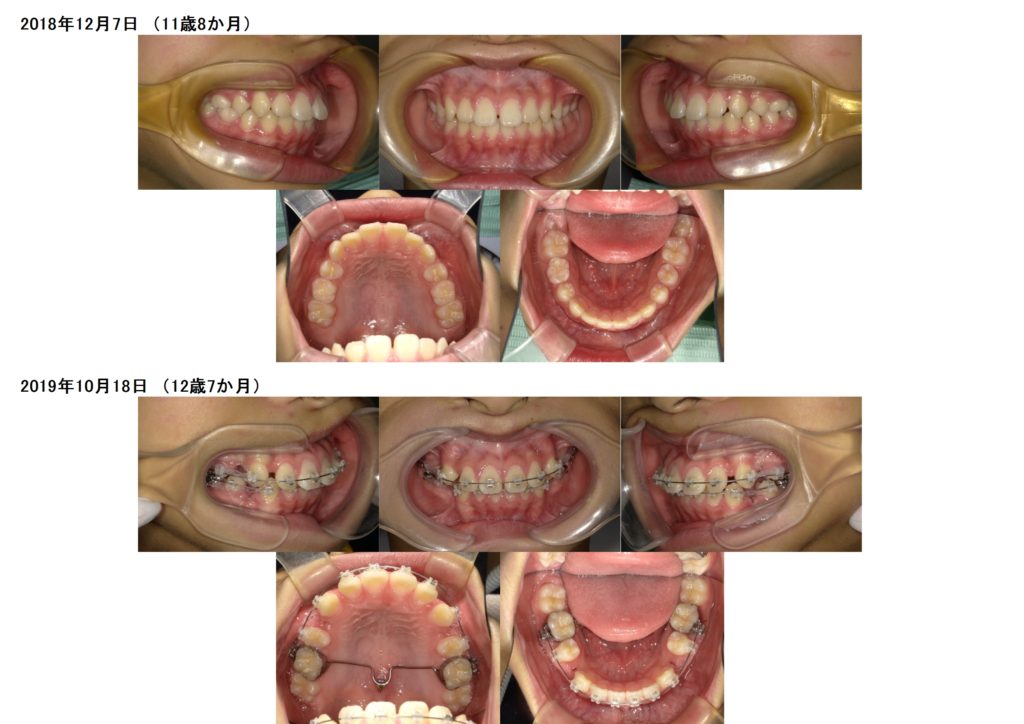

↑この患者様は上下の歯を2本ずつ抜歯しています。

上の顎にアンカースクリューを使用し、抜歯した際に6番目の歯が寄ってこないためにしています。

このように土台を整えつつ、ブラケットを使用し調整をしていきます。

奥歯の噛み合わせを確立したら、あとは前歯部の噛み合わせを合わせ引っ込めていきますよ

隙間が埋まったら治療が終わりです☆